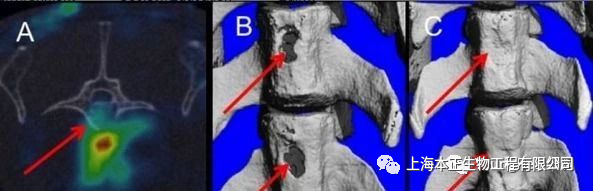

实验室的研究人员给予实验动物对象为期 21 天的甲状旁腺激素注射,同时使用取自脐带 5 个单位的干细胞治疗。结果表明,联合治疗可以显著增强干细胞的迁移到骨折部分,并且促进骨折处形成新的、健康的骨骼(图 1)。

图1  A 干细胞靶点的脊柱骨折;B 两个脊椎骨折;C 干细胞与甲状旁腺素治疗 8 周后修复的脊柱